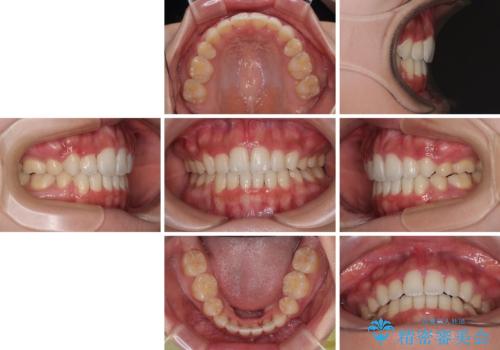

横顔の印象を改善したい ワイヤー装置での抜歯矯正

- 口元の突出感と口の閉じにくさを気にして来院された患者様です。

上下左右第一小臼歯4本を抜歯し、ワイヤー装置にて口元を引っ込めるよう矯正治療を行うこととしました。

口元の突出感が改善されてことで、下唇に引っかかっていた上顎前歯も気にならなくなりました。